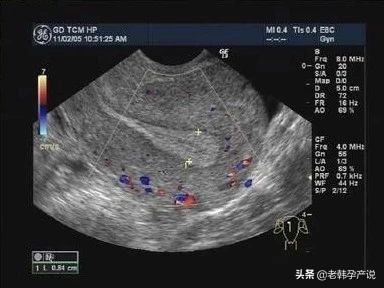

上图是优势卵泡直径达到18mm时子宫内膜的图像,呈明显三线征,中间的宫腔线回声强,上面的一条线以及下面一条线与宫腔线之间的组织呈低回声。

子宫内膜除了厚与薄外,还有很重要的一点:就是形态。不是单纯厚就好,还要有好的形态。好的子宫内膜比较丰盈,有三条线,叫三线征,就像人的嘴巴。中间的一条线叫宫腔线,宫腔线最好从宫颈处连续上升至宫底,不要有中断,有明显的中断通常是宫腔粘连的表现,